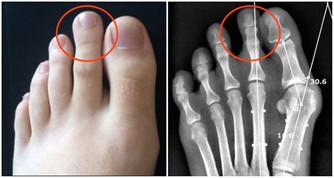

1. 腿部腫脹疼痛

如果血栓源於腿部,當它形成時,靜脈中會出現腫脹,這會導緻小腿肌肉疼痛。更糟糕的是,小腿組織很厚,因此身體系統難以消除血栓。所以,如果你發現自己吃了消腫藥卻不起作用,那就說明可能存在血栓。

9. 腳和小腿疼痛

小腿上的深靜脈血栓,會造成嚴重的疼痛,使人步行困難並且坐著也會疼。不僅如此,腳部疼痛也是其後果之一,由於血栓妨礙血液流向足部,導致足部缺氧,造成嚴重不適。